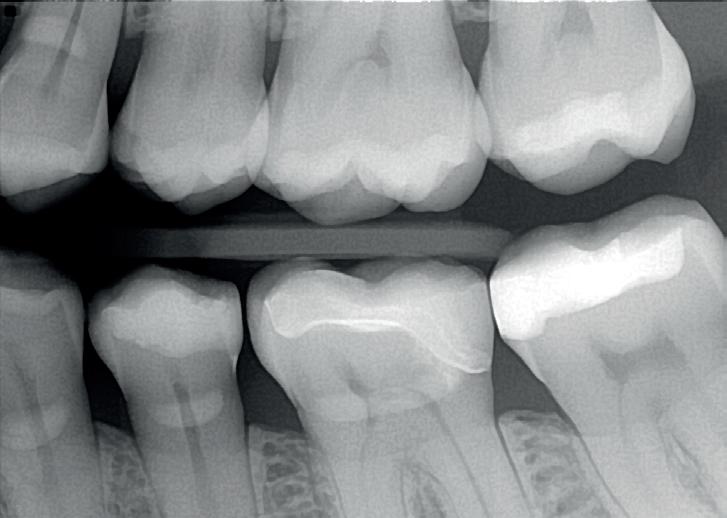

Het cariësproces in de 25 was mesiaal tot in het dentine voortgeschreden zoals zichtbaar op de bitewing en de donker doorschemerende randlijst. Er werd besloten tot restauratie.

Als laatste stap van het vulproces wordt een minimale hoeveelheid flowable en hieroverheen een laag stug hoger gevuld composiet, in dit geval Tetric PowerFill, aangebracht. Porositeiten en oneffenheden worden door deze combinatie van vloeibaar en stug materiaal perfect opgevuld. Voorafgaand aan de uitharding wordt het composiet zorgvuldig in vorm gebracht. Het materiaal geeft je 4 minuten de tijd om dit te doen. Des te beter de vorm des te minder afwerking er nodig is. Het gebruikte composiet heeft net zoals de Tetric PowerFlow de eigenschap dat deze met de Bluephase PowerCure tot dieptes van 4 mm in 3 seconden uitgehard kan worden. Dit kan vooral heel efficiënt zijn bij grotere defecten, waarbij de 2 mm grens van conventioneel uit te harden composiet overschreden wordt. Daarbij verandert ook de translucentie van het materiaal tot onder de 10%. Er is daarbij een kleuromslag waarneembaar van een beetje gelig naar een mooie tandkleur.

Er is een vereenvoudigde anatomie aangebracht zonder staintechniek en secundaire/tertiaire fissuren. Het contactpunt is goed hersteld en de randen zijn goed te inspecteren. De optische integratie voldoet goed. De getoonde restauratie werd in 15 minuten voltooid. Diepere restauratie randen en grotere caviteiten kunnen met dezelfde methode worden behandeld, doch zullen meer tijd in beslag nemen.